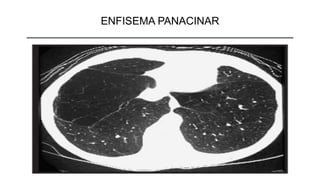

ENFISEMA PANACINAR

➢Acomete o todo dos ácinos, com dilatação e destruição de seus

alvéolos.

➢Desenvolvem-se fenestras entre os alvéolos

➢É o tipo de enfisema mais disseminado e grave e, conseqüentemente,

o que mais resultará em doença clinicamente significativa

➢Associação com enfisema centrolobular.